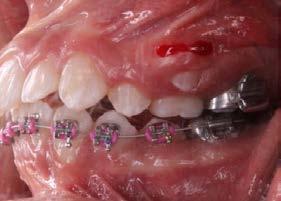

Por lo que se propone procedimiento quirúrgico con la evidente comunicación oroantral al realizar las extracciones de los órganos dentales involucrados. Previa asepsia y antisepsia, colocación de campos estériles, extracción de segundo y tercer molar superior derecho e incisión envolvente con descarga mesial (Figura 3), rotación y afronte mediante puntos simples de la bola adiposa de Bichat para el cierre de la comunicación oroantral (Figura 4), farmacoterapia con base en amoxicilina con ácido clavulánico. Una semana después refiere no presentar rinorrea y mejoría al 100% de la obstrucción. Posterior a 6 meses de evolución clínica (Figura 5) y radiográficamente (Figura 6), no se observa comunicación oroantral o paso de líquidos de la cavidad oral a la cavidad nasal.

Figura 5. Fotografía oclusal de 6 meses de evolución.

6 meses posterior a la cirugía.